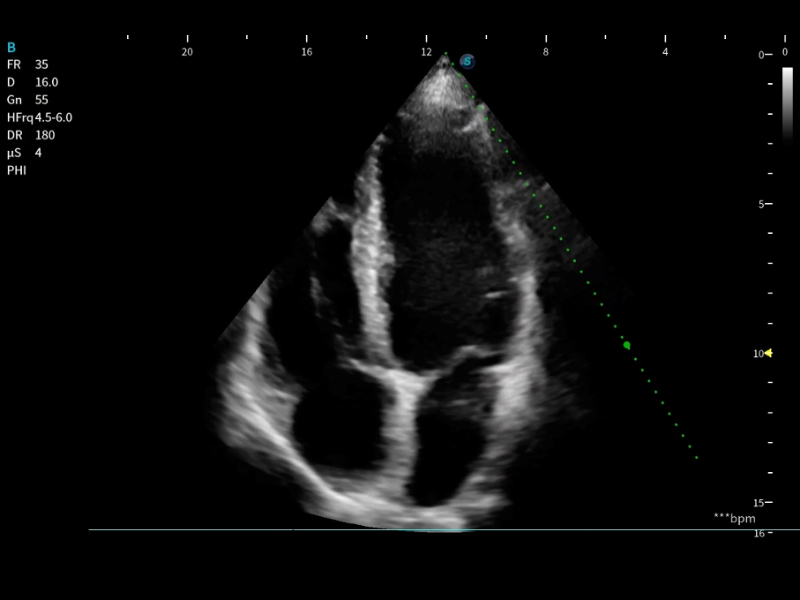

作为开立医疗全新打造的高端床旁笔记本超声,E11不仅具备卓越的图像质量,同时搭载全面高效的自动测量工具,助力医生实现更快速、更精准的床旁诊断。

E11搭载了丰富的自动化测量工具,以及专为POC科室定制的高级功能;同时配备了为急诊医师量身打造的 SonoFast急重症超声流程,以帮助临床医生最大限度的提升工作效率